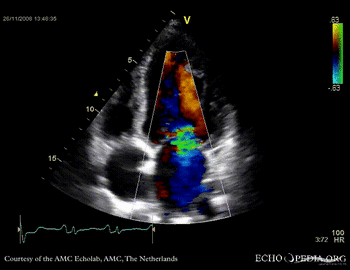

Dilated cardiomyopathy with severe mitral valve regurgitation

Courtesy of: J. Vleugels, AMC, The Netherlands